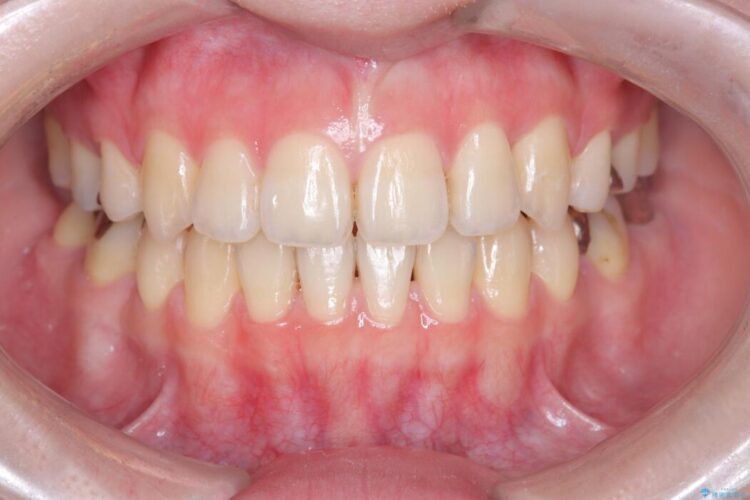

切らない・腫れにくい短期間治療【1DAYインプラント】

右上の奥歯に根尖病変があり、長期的に安定した治療をご希望されたため、インプラント治療を行いました。

治療期間(治療回数):3ヶ月(2~5回) | 概算治療費:638,000円(税込)